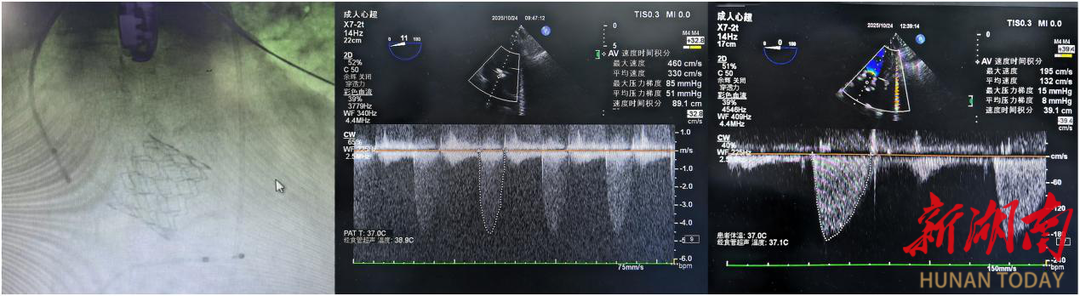

10月20日,几名神色紧张的家属推着一位大口喘气、全身浮肿的男子到湘西州人民医院心血管内三科,操着浓郁的土家普通话呼喊着“医生快救命”。该科主任罗亚雄、医生雷鸣看到病情危重,就一同查看病人。在询问相关病史、进行相关体格检查和阅读相关资料后,两人倒吸一口冷气,原来这是一名极危重症主动脉瓣膜狭窄患者,心脏彩超提示主动脉瓣重度狭窄合并中度关闭不全,心脏明显扩大(LVED66mm),左室射血分数不足25%,现在血压偏低,靠血管活性药物维持,且已经在县级医院反复救治,常规药物治疗已无明显效果,心脏瓣膜置换势在必行,但现有心功能对于麻醉和手术都有极大挑战。

术后患者立即转到重症监护室,经团队严密监护与逐步测试,顺利撤除各项生命支持设备。术后第三天转回普通病房。患者心脏彩超指标也明显改善,复查心脏彩超指标明显改善,左室舒张末内径从术前66mm下降至60mm,射血分数从术前25%显著提升至41%,其他各项生化指标以及生命体征均明显改善。经过密切围手术期管理和心脏康复治疗,患者恢复良好,即将出院。